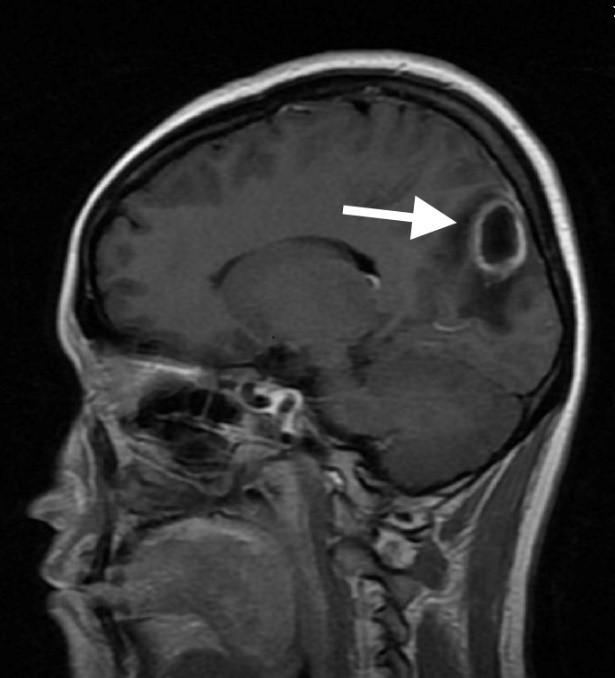

脑子里长了圆圆的脓肿

还伴随着严重的脑水肿

大脑里的病灶清晰可见

接诊的林邵奇医师详细地询问了病史,拿着小鱼的磁共振片子仔细端详起来,并向主管的陈景森和严锋副主任医师进行了详细的病情汇报。“从片子上看,小鱼的大脑里的确潜伏着一个圆圆的病灶。”陈景森主任说,“她得的是‘脑脓肿’,这种疾病就像在人的大脑里面裹了一包脓液,十分凶险。”

“从小鱼的片子上看,病灶体积大,周围还伴有严重的脑水肿,需要开颅手术切除病灶。”严锋主任说,“但是这个脑脓肿是由什么原因造成的,始作俑者到底是什么,却还是一桩悬案。”